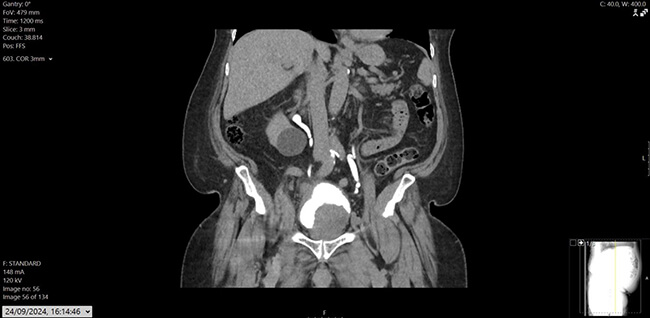

His prostate specific antigen (PSA) had decreased from 43.6ug/L in December 2022 to 0.02ug/L. He also had a history of hypertension, osteoarthritis, and hypercholesterolemia, with mixed lower urinary tract symptoms (LUTS), managed on tamsulosin. Flexible cystoscopy revealed a large mass on the left lateral bladder wall, with CT imaging confirming a bladder mass and thickening at the bladder dome. Mild pericaecal fat stranding and lymphadenopathy were also noted (Figure 1, 2 and 3). Preoperative blood work showed stable parameters.

Figure 1: CT Urogram - coronal image showing large intraluminal bladder mass arising from the left lateral wall; another mass like bladder wall thickening noted in the bladder dome extending into the right lateral aspect.